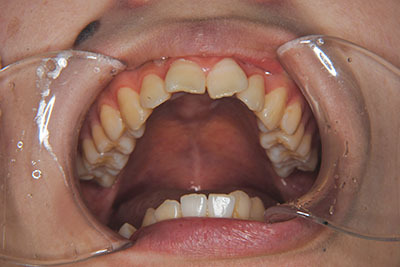

おとなの方でも矯正治療をあきらめないでください!

子供の頃に矯正治療を行う方が治療期間が短く済むというのは、確かですが、矯正治療は患者様の意識も重要です。

いくら歯が動き易くとも、本人がやる気でなければ効果は出ませんし、むし歯発生のリスクも高まります。おとなの方は顎の成長が終わっているため、治療の計画が立てやすいとも言えます。「もう大人だから…」とあきらめず、一度ご相談ください。